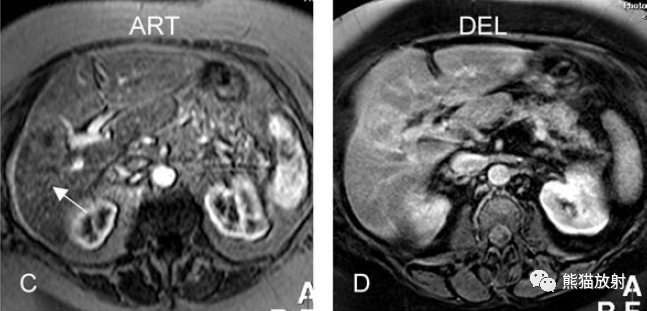

增强动脉期(ART):不均质强化;

-

延迟期(DEL):部分廓清,部分持续强化。

胆囊癌。A~D图:上方层面,表现如上所述,形成肿物侵及肝脏。E、F图:下方层面示胆囊壁不规则增厚,明显不均质强化。

胆囊癌。病灶以胆囊为中心侵及肝脏,明显弥散受限,由于病灶内含结缔组织/纤维成分(T2低信号)导致肝被膜内陷,增强扫描动脉期明显不均质强化,延迟期中心纤维成分延迟强化。表现类似肝内胆管细胞癌。